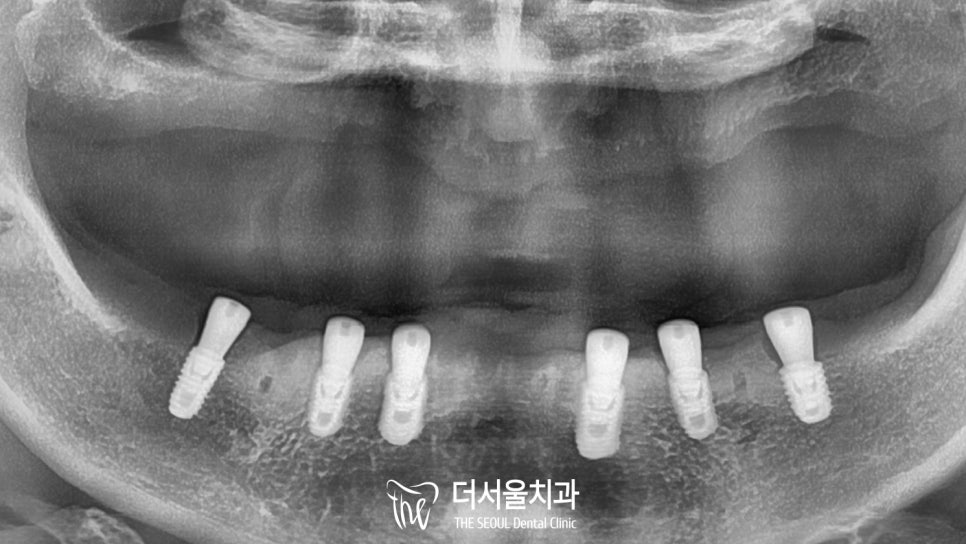

CT를 통해 확인해 보니 정확하게 심어져 있네요.

골융합이 잘 이루어질 수 있을까,

초기 고정력을 얻을 수 있을까

걱정이 들었지만 다행히 깔~끔하게 고정을 얻고 있었습니다.